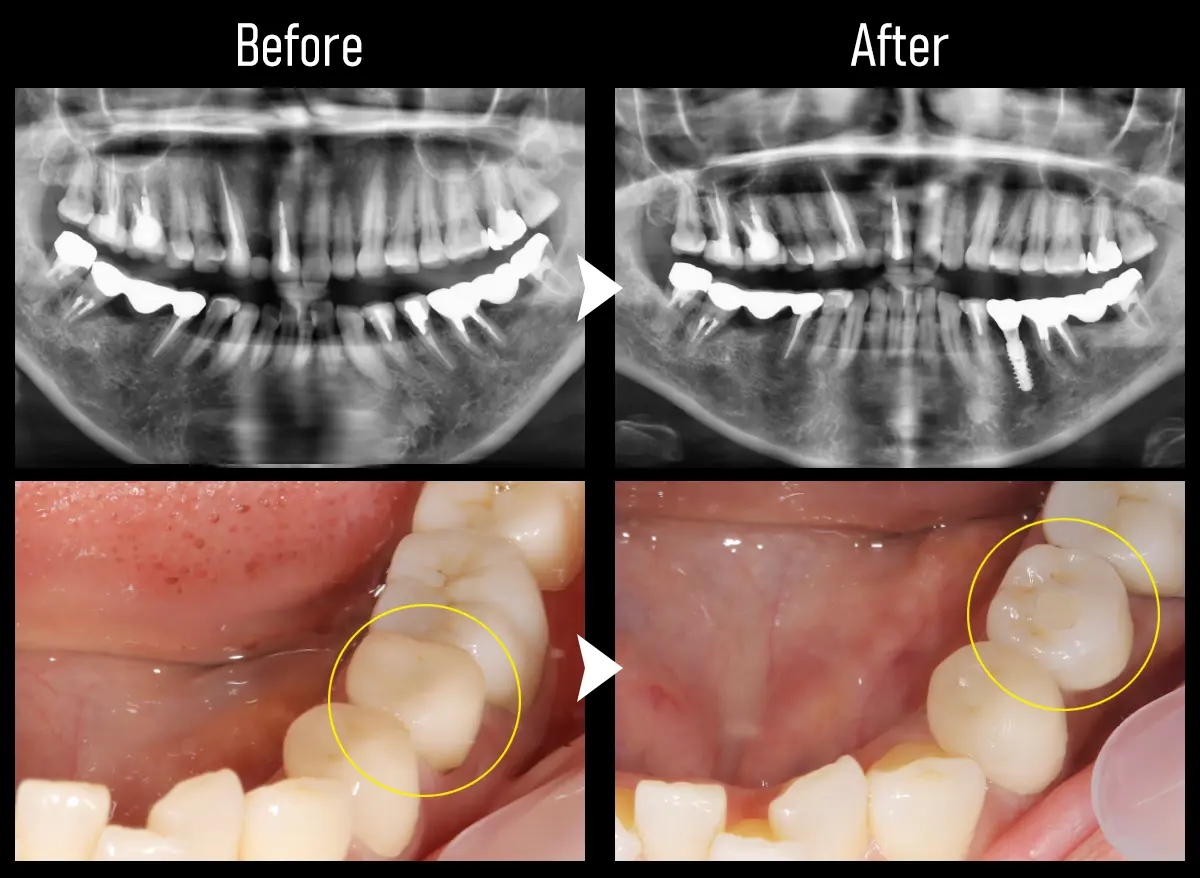

CASE:小臼歯1本

主訴 歯が折れてると言われて痛い

治療内容 下顎左5番にインプラント治療

標準費用(自費) 55万円